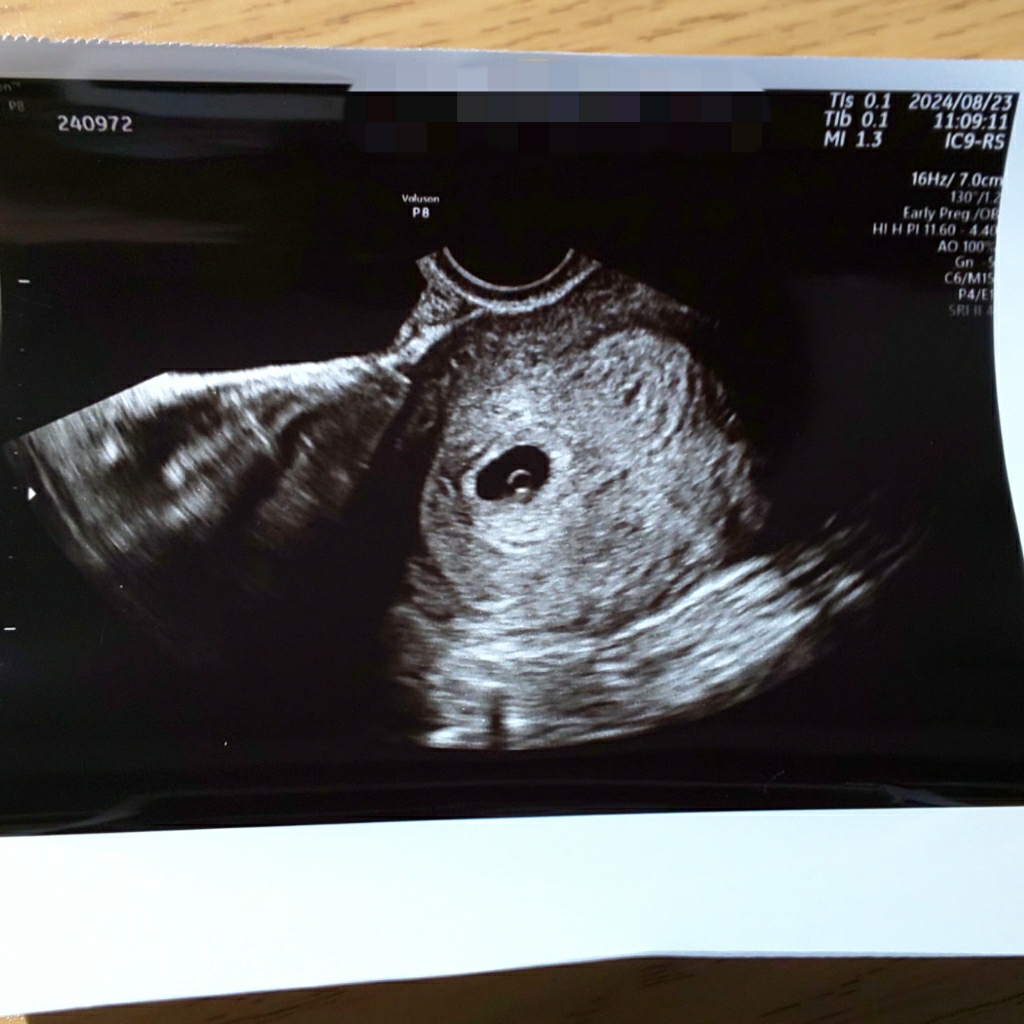

08/23 5w6d

生理が遅れたため妊娠検査薬を使い陽性。翌日に産婦人科を受診し胎嚢が確認できました。子宮内妊娠とのことでひとまず安心。直近の飲み会で記憶が飛ぶほど飲酒してましたがこの段階では問題なし。次回の検診で心拍確認できるか不安になりながら過ごしていくことになります…。ちなみに6週に入ってからつわりが本格化しました。